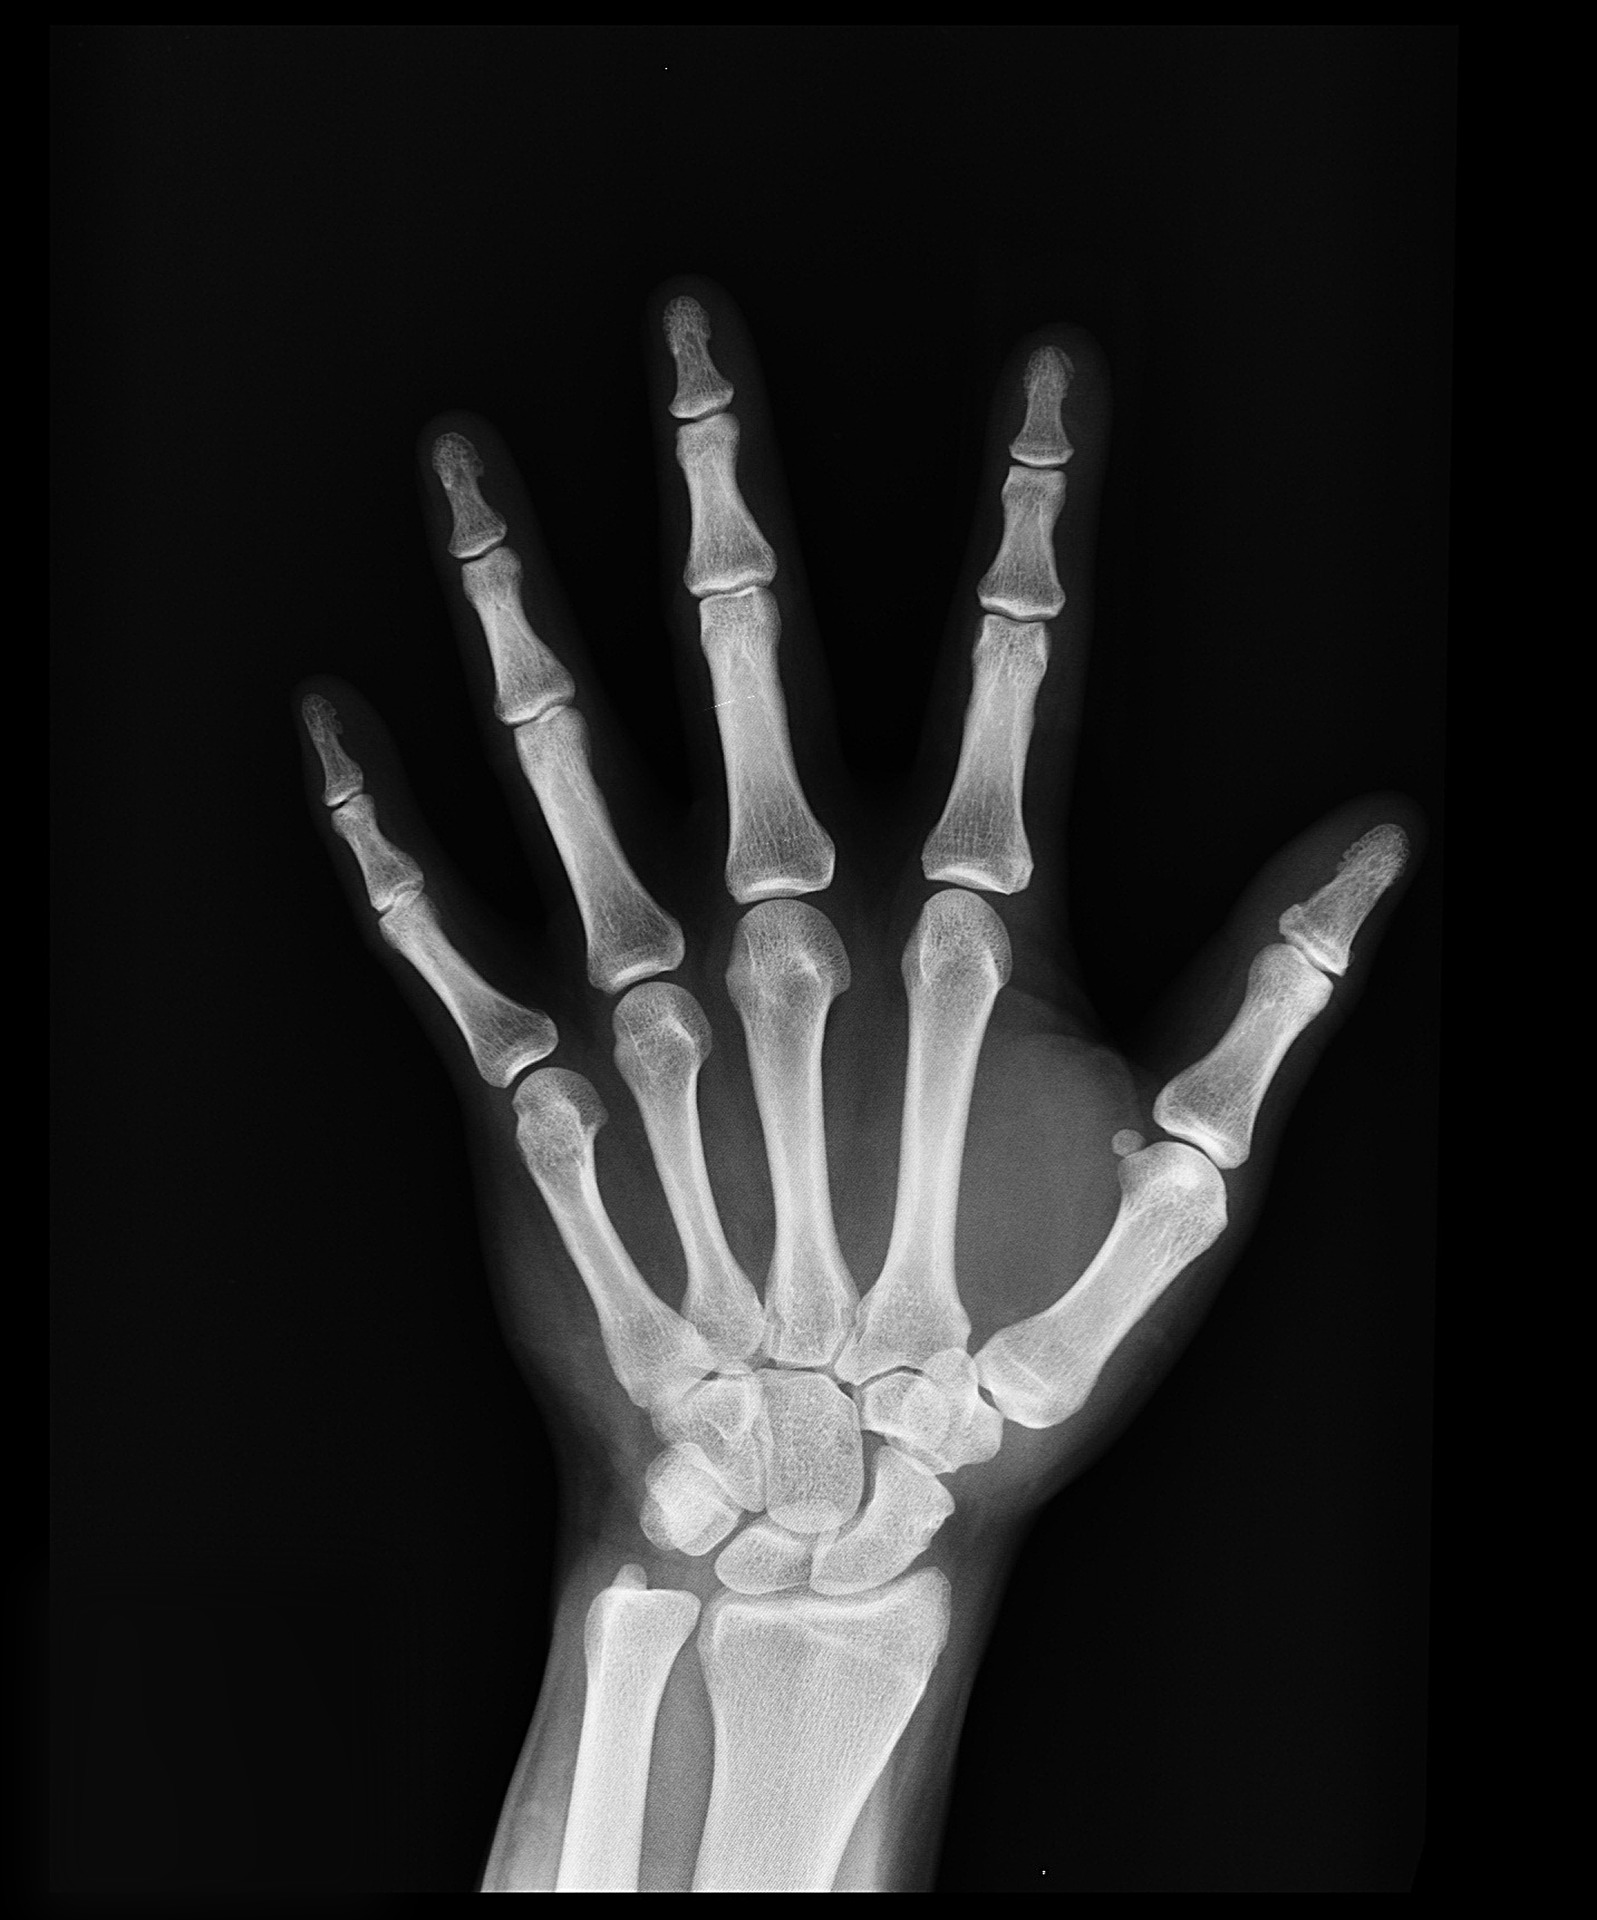

Reduced risk of bone breakage and bone diseases

Another health benefit of using CBD products is the reduced risk of bone breakage and bone diseases. Bone metabolism is a complex process and it is facilitated by the cannabinoids. This replacement of old bone material with new one happens constantly and it is the reason for preserving strong, healthy bones. Every imbalance in the metabolism may be the reason for bone diseases such as osteoporosis, as well as osteoarthritis. CBD products also help the healing process of bones which have already been broken. This is possible because CBD helps build a fracture callus which is stronger and the likelihood of re-fracturing the bone afterward is reduced up to 50%. This fact is proven by several pieces of research.